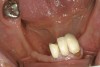

A patient with no change in root-surface quality (Figure 1) will present with gingival recession that exposes the root surfaces and no change due to disease is noted. Clinically, the root surfaces are firm, smooth, and velvety upon exploration. No color changes are noted.

Figure 1  This patient presented with generalized gingival recession of the mandibular anterior teeth. There were no changes in the root surfaces that would indicate the beginning of the demineralization process. Although no surface demineralization process had occurred, these root surfaces would respond to remineralization therapy. The positive changes may include: hard, shiny root surfaces and a reduction in dentinal hypersensitivity.

Figure 1